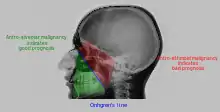

Interpretation of results

| Pathology | Observation |

|---|---|

| None (Normal) |

|

| Maxillary sinusitis[2] | ![]() Differentiating pathology in maxillary sinus

| Polyp |

| Malignancy |

![]() Onhgren's line